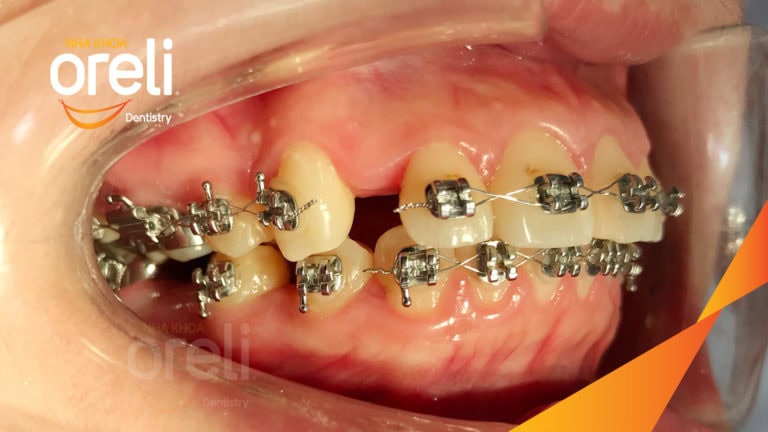

Ca niềng răng sai khớp cắn hạng 3 móm chen chúc kèm di gần răng số 7 8 thay thế răng 6 ở Oreli Niềng răngChen chúcDi gần răng 7 8Móm Xem thêm